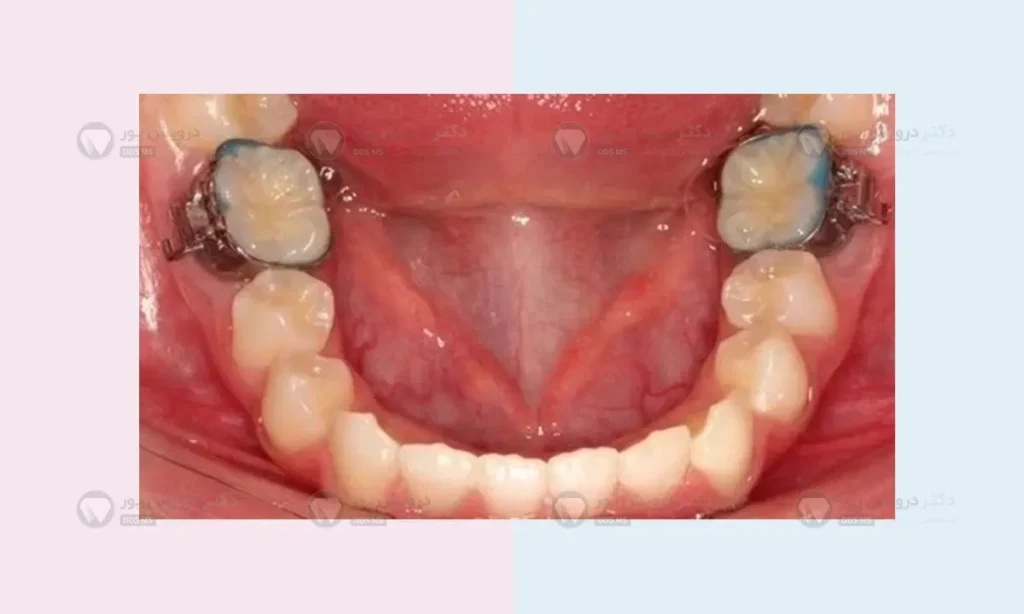

اگر بخواهیم خیلی ساده بگوییم، بند ارتودنسی یک حلقه یا کمربند از جنس فولاد ضدزنگ پزشکی است که به طور کامل دور دندان های آسیاب بزرگ (دندان های انتهای فک) شما قرار می گیرد و آن را در آغوش می گیرد. برخلاف براکت ها که فقط روی سطح جلویی دندان متصل می شوند، این حلقه های فلزی کاملاً دندان را احاطه می کنند.

روی این حلقه های فلزی، شیارها و قلاب های کوچکی جوش داده شده است. این شیارها دقیقاً همان جایی هستند که سیم اصلی ارتودنسی از آن ها عبور می کند. به زبان ساده، این بندها نقش یک لنگرگاه بسیار قوی و محکم را در انتهای فک شما بازی می کنند. چرا؟ تا کل سیستم بتواند به درستی کار کند و نیروی لازم برای حرکت دندان ها را تأمین نماید.

حدود یک هفته قبل از روز نصب، دکتر یک کش لاستیکی کوچک (معمولاً آبی رنگ) را بین دندان های آسیاب شما قرار می دهد. وظیفه این کش این است که در طول یک هفته، دندان ها را در حد چند دهم میلی متر از هم دور کند تا فضا برای نشستن حلقه فلزی باز شود. این مرحله ممکن است در دو سه روز اول کمی دردناک باشد و حس کنید تکه گوشتی بین دندان هایتان گیر کرده است، اما برای ادامه کار کاملاً ضروری است.